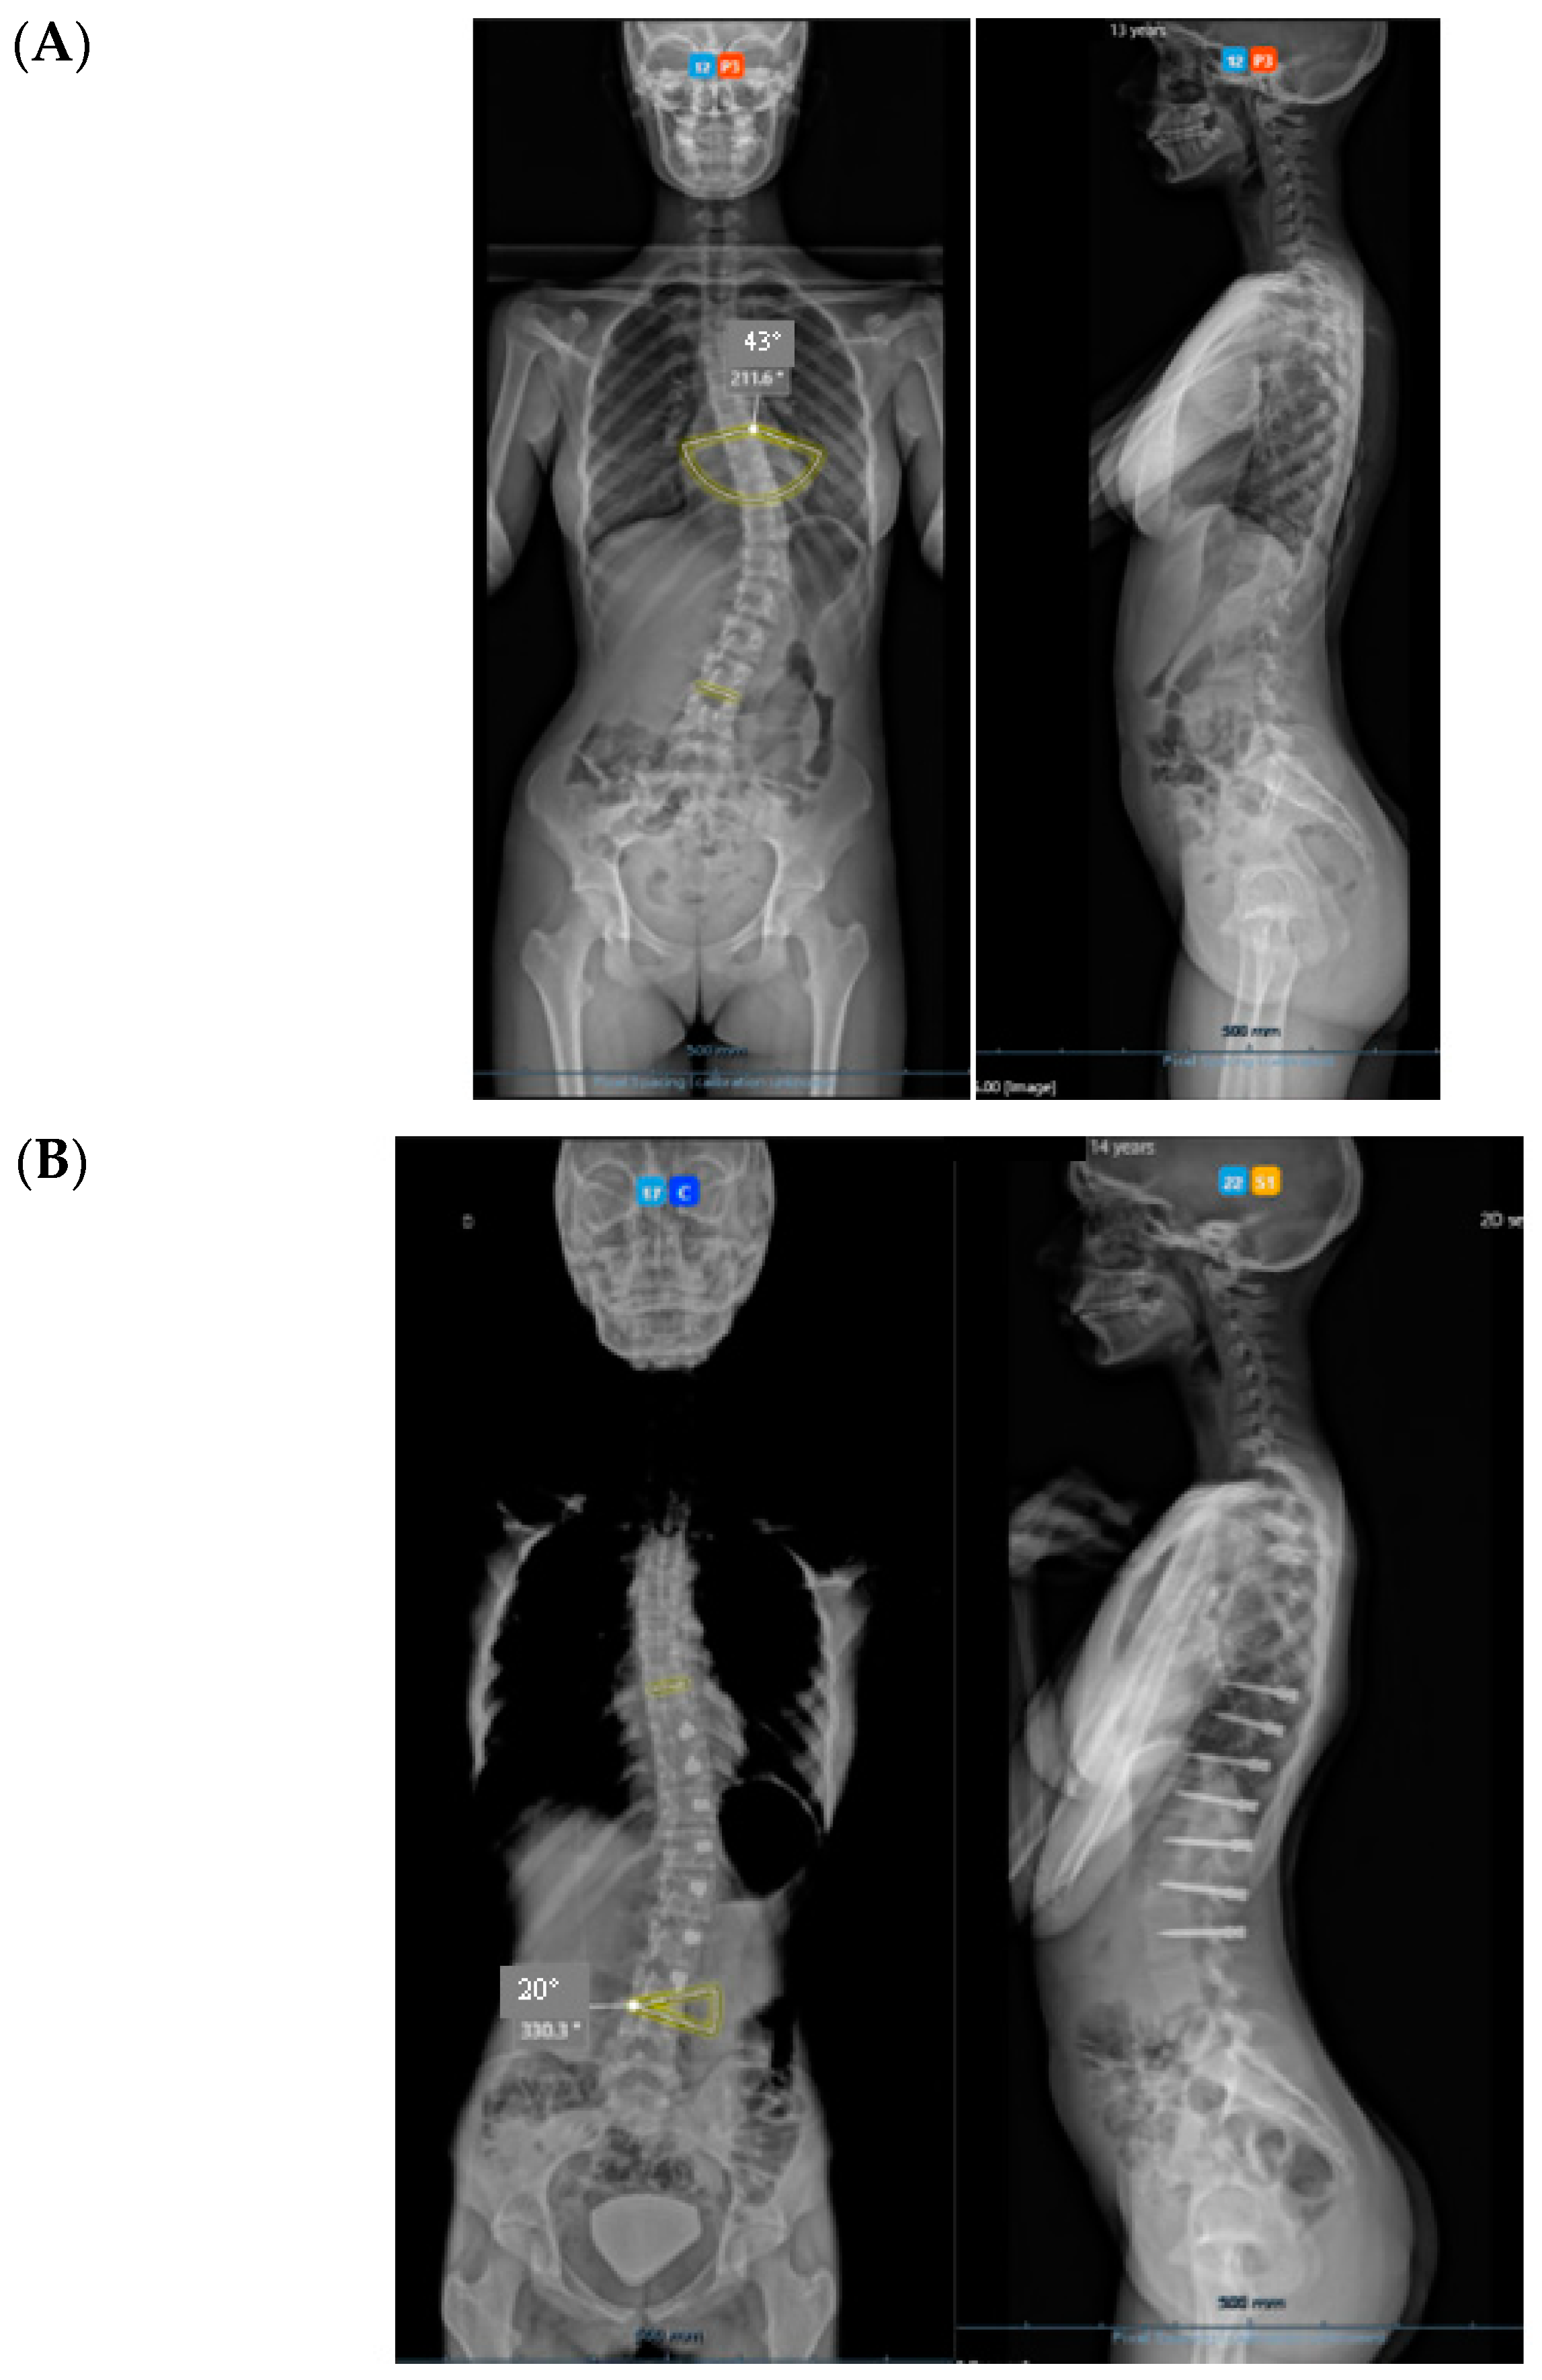

Figure 9.

Over-correction. (A) Pre-op (left) + 18-month FU (curvature apex corrects to the opposite side) (right). (B) Post tether release. (C) Immediate post-op erect radiograph.

3.1. Complications

The only case with a 15-month follow up progressed to coronal over-correction and had to be revised (under local anaesthetic) for tether release at four levels (Figure 9A,B). Since then, she has been doing well clinically and radiologically. This complication may have happened because correction obtained at the index procedure was too much, with a Cobb angle of 13.6° in the immediate post-operative erect radiograph (pre-op Cobb angle 56.7°) in a girl rated Sanders 3 (Figure 9C).